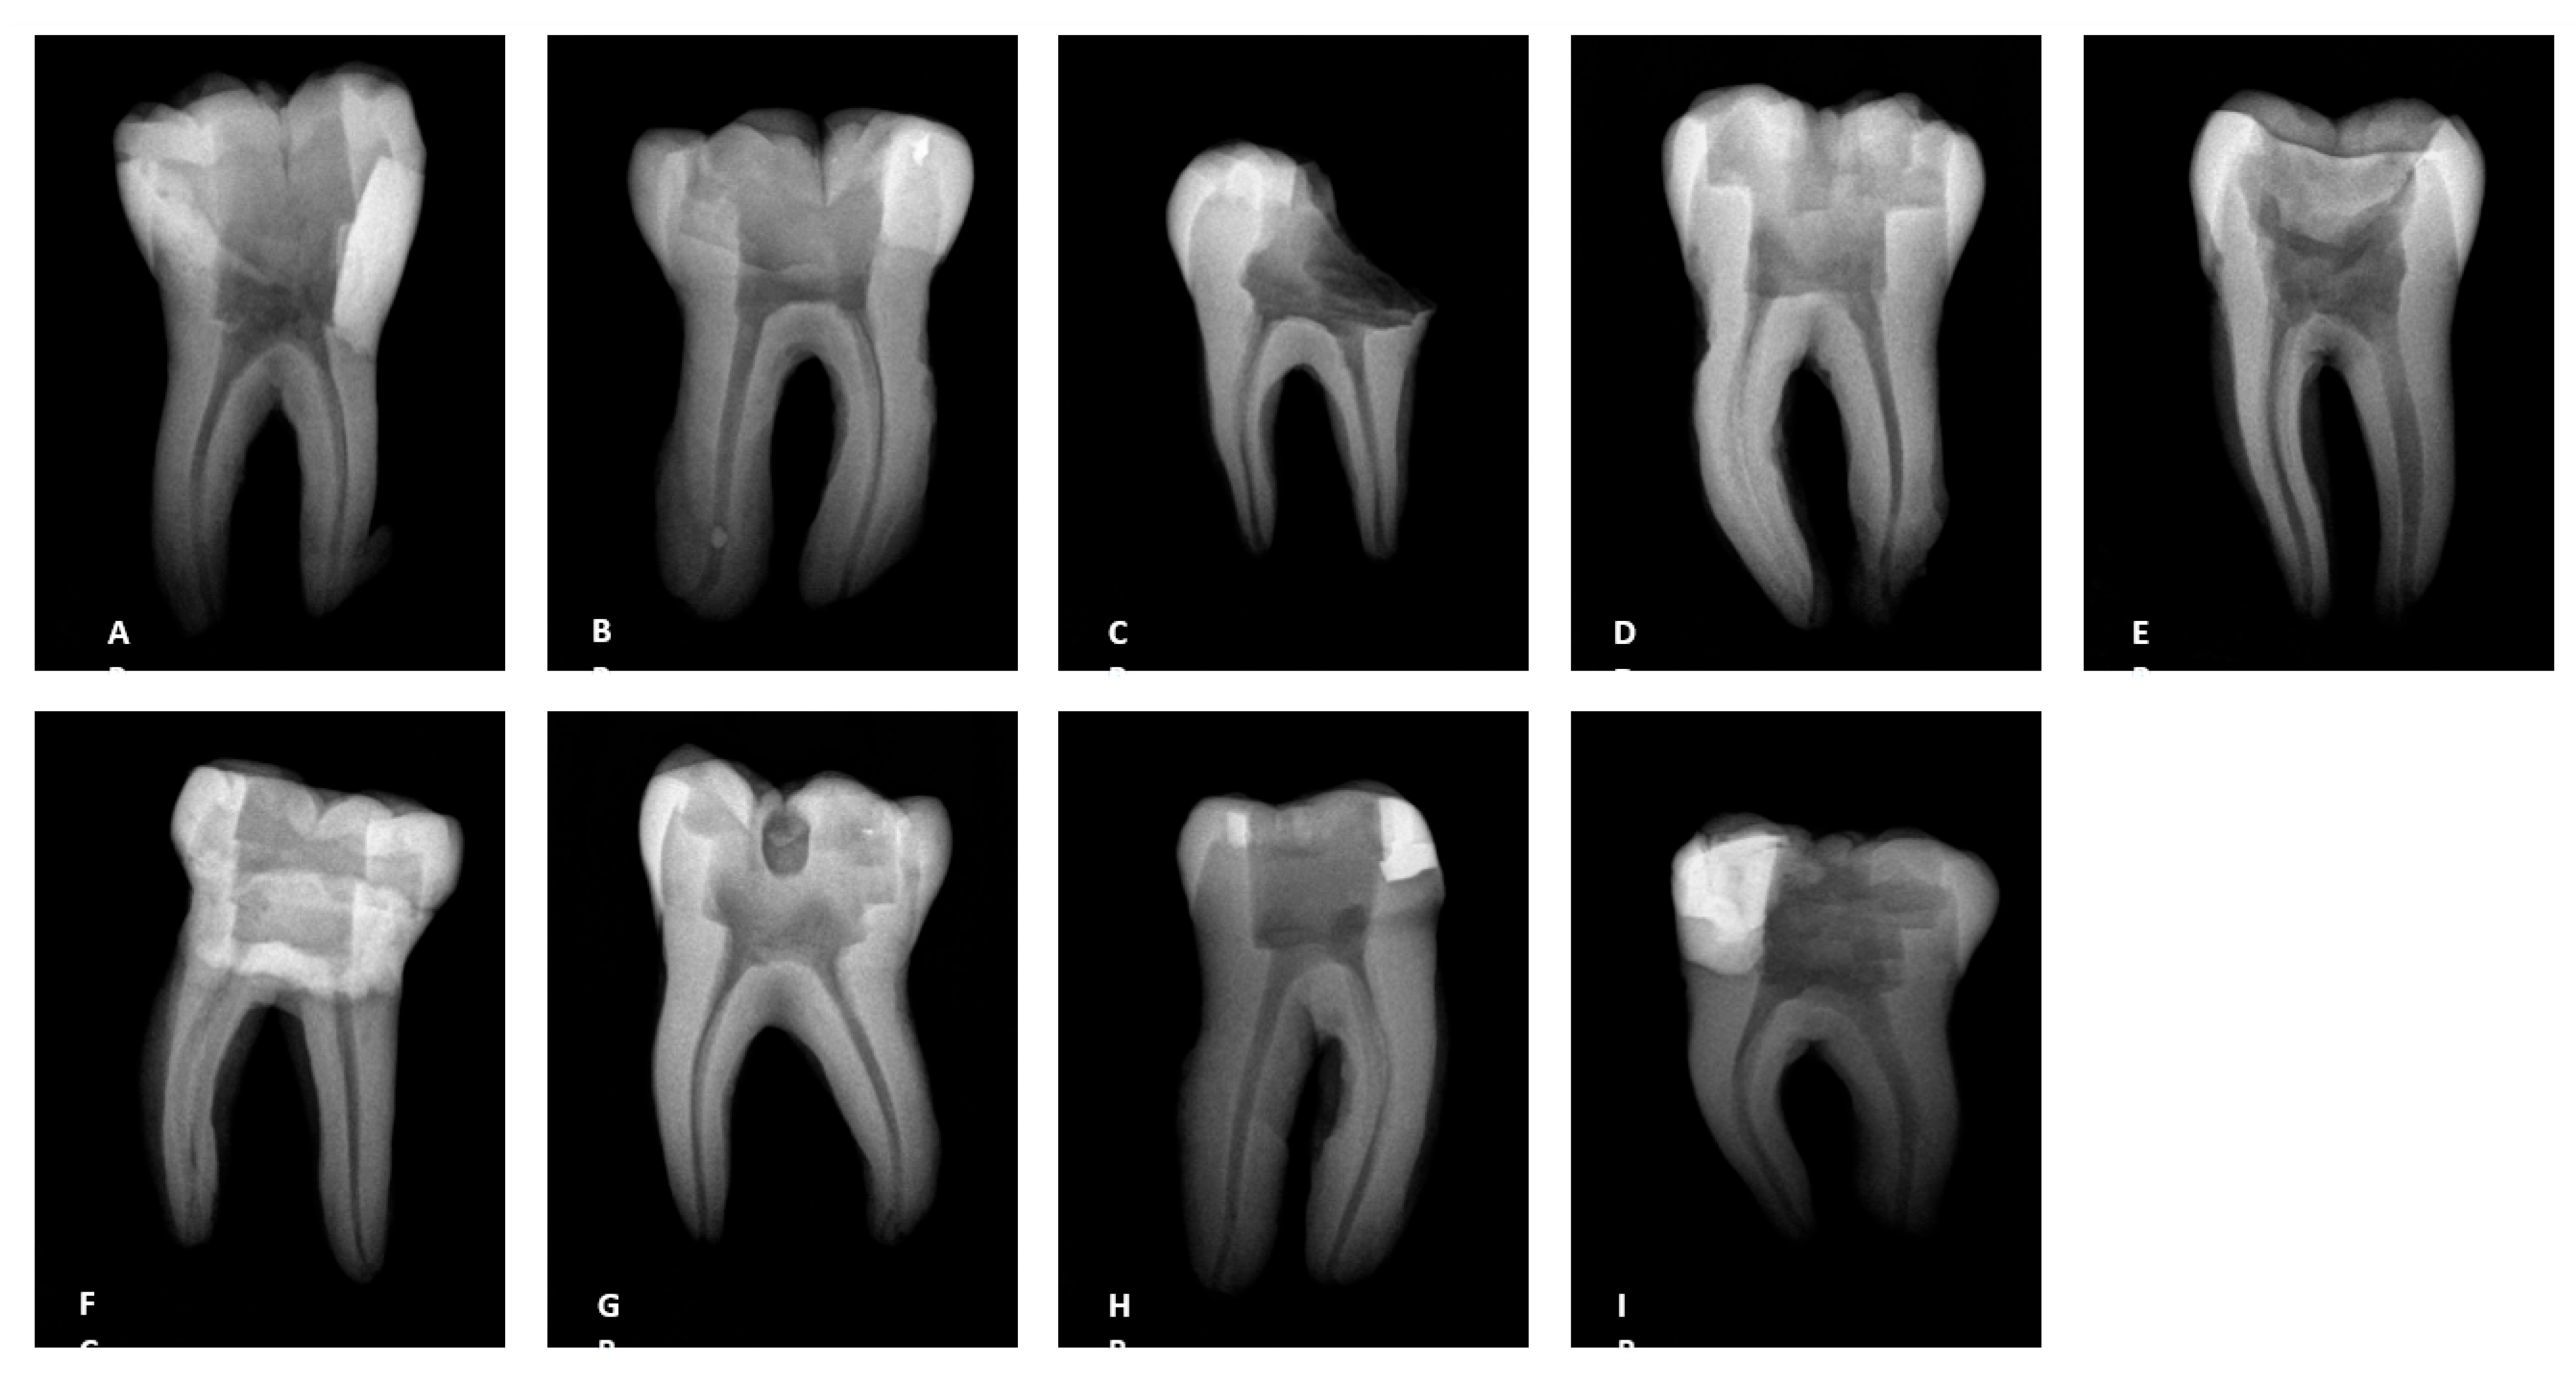

2. Material and Methods

3.2. Radiographs